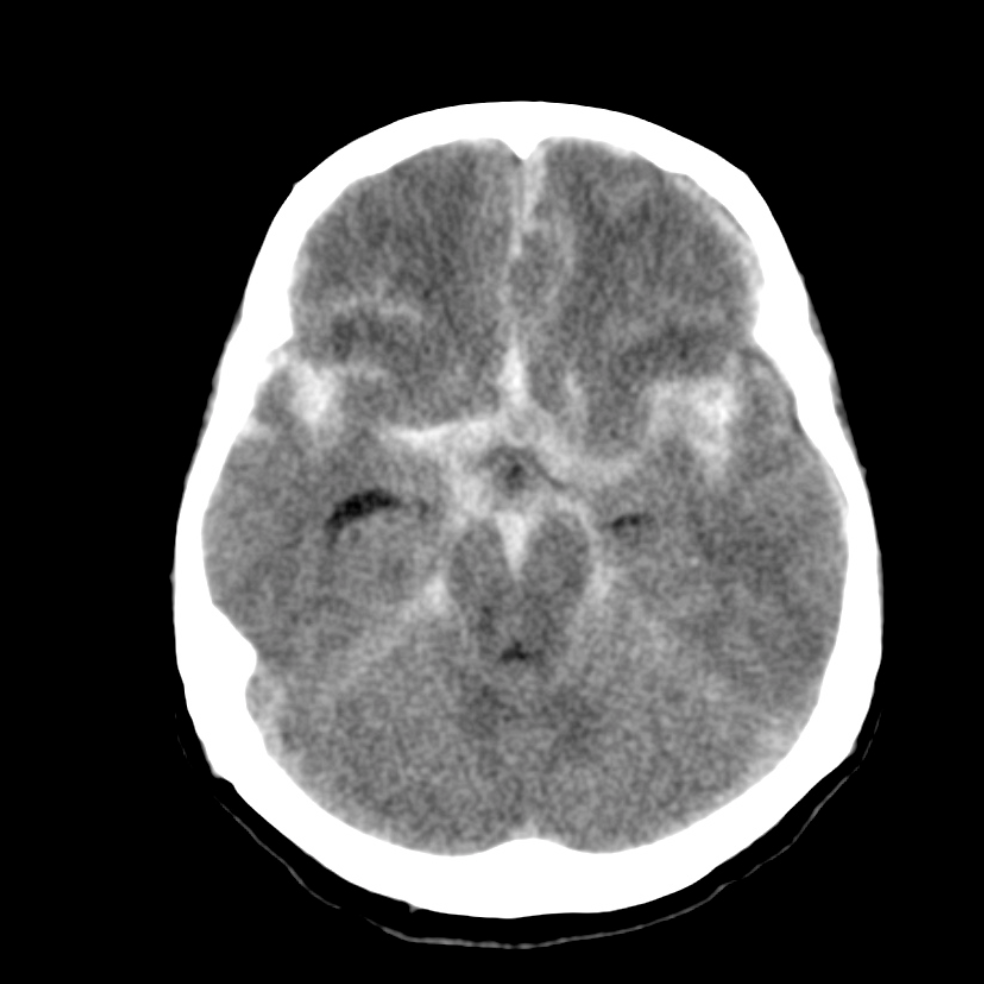

蜘蛛網膜下出血

出血位於蜘蛛網膜和軟腦膜之間,創傷、腦血管動脈瘤破裂是常見成因。患者會忽然覺得劇烈頭痛。治療上主要是控制血壓,減少腦水腫。